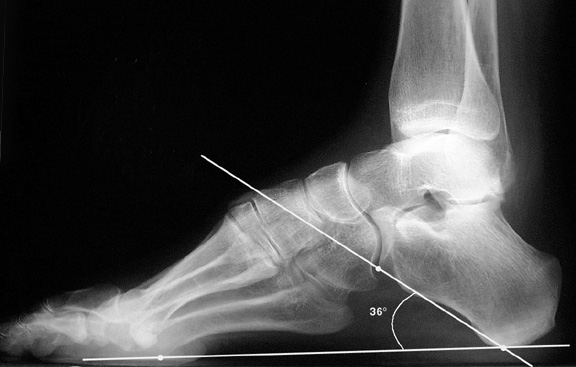

Increased calcaneal pitch angle

When the predominate component of pes cavus originates in the hindfoot, it often manifests as a high calcaneal pitch on lateral radiographs. Measurement of calcaneal pitch has been discussed above. 18 to 20° is generally considered normal (12), although measurements ranging from 17 to 32° have been reported to be normal (5).

b. Abnormally high calcaneal pitch consistent with pes cavus.